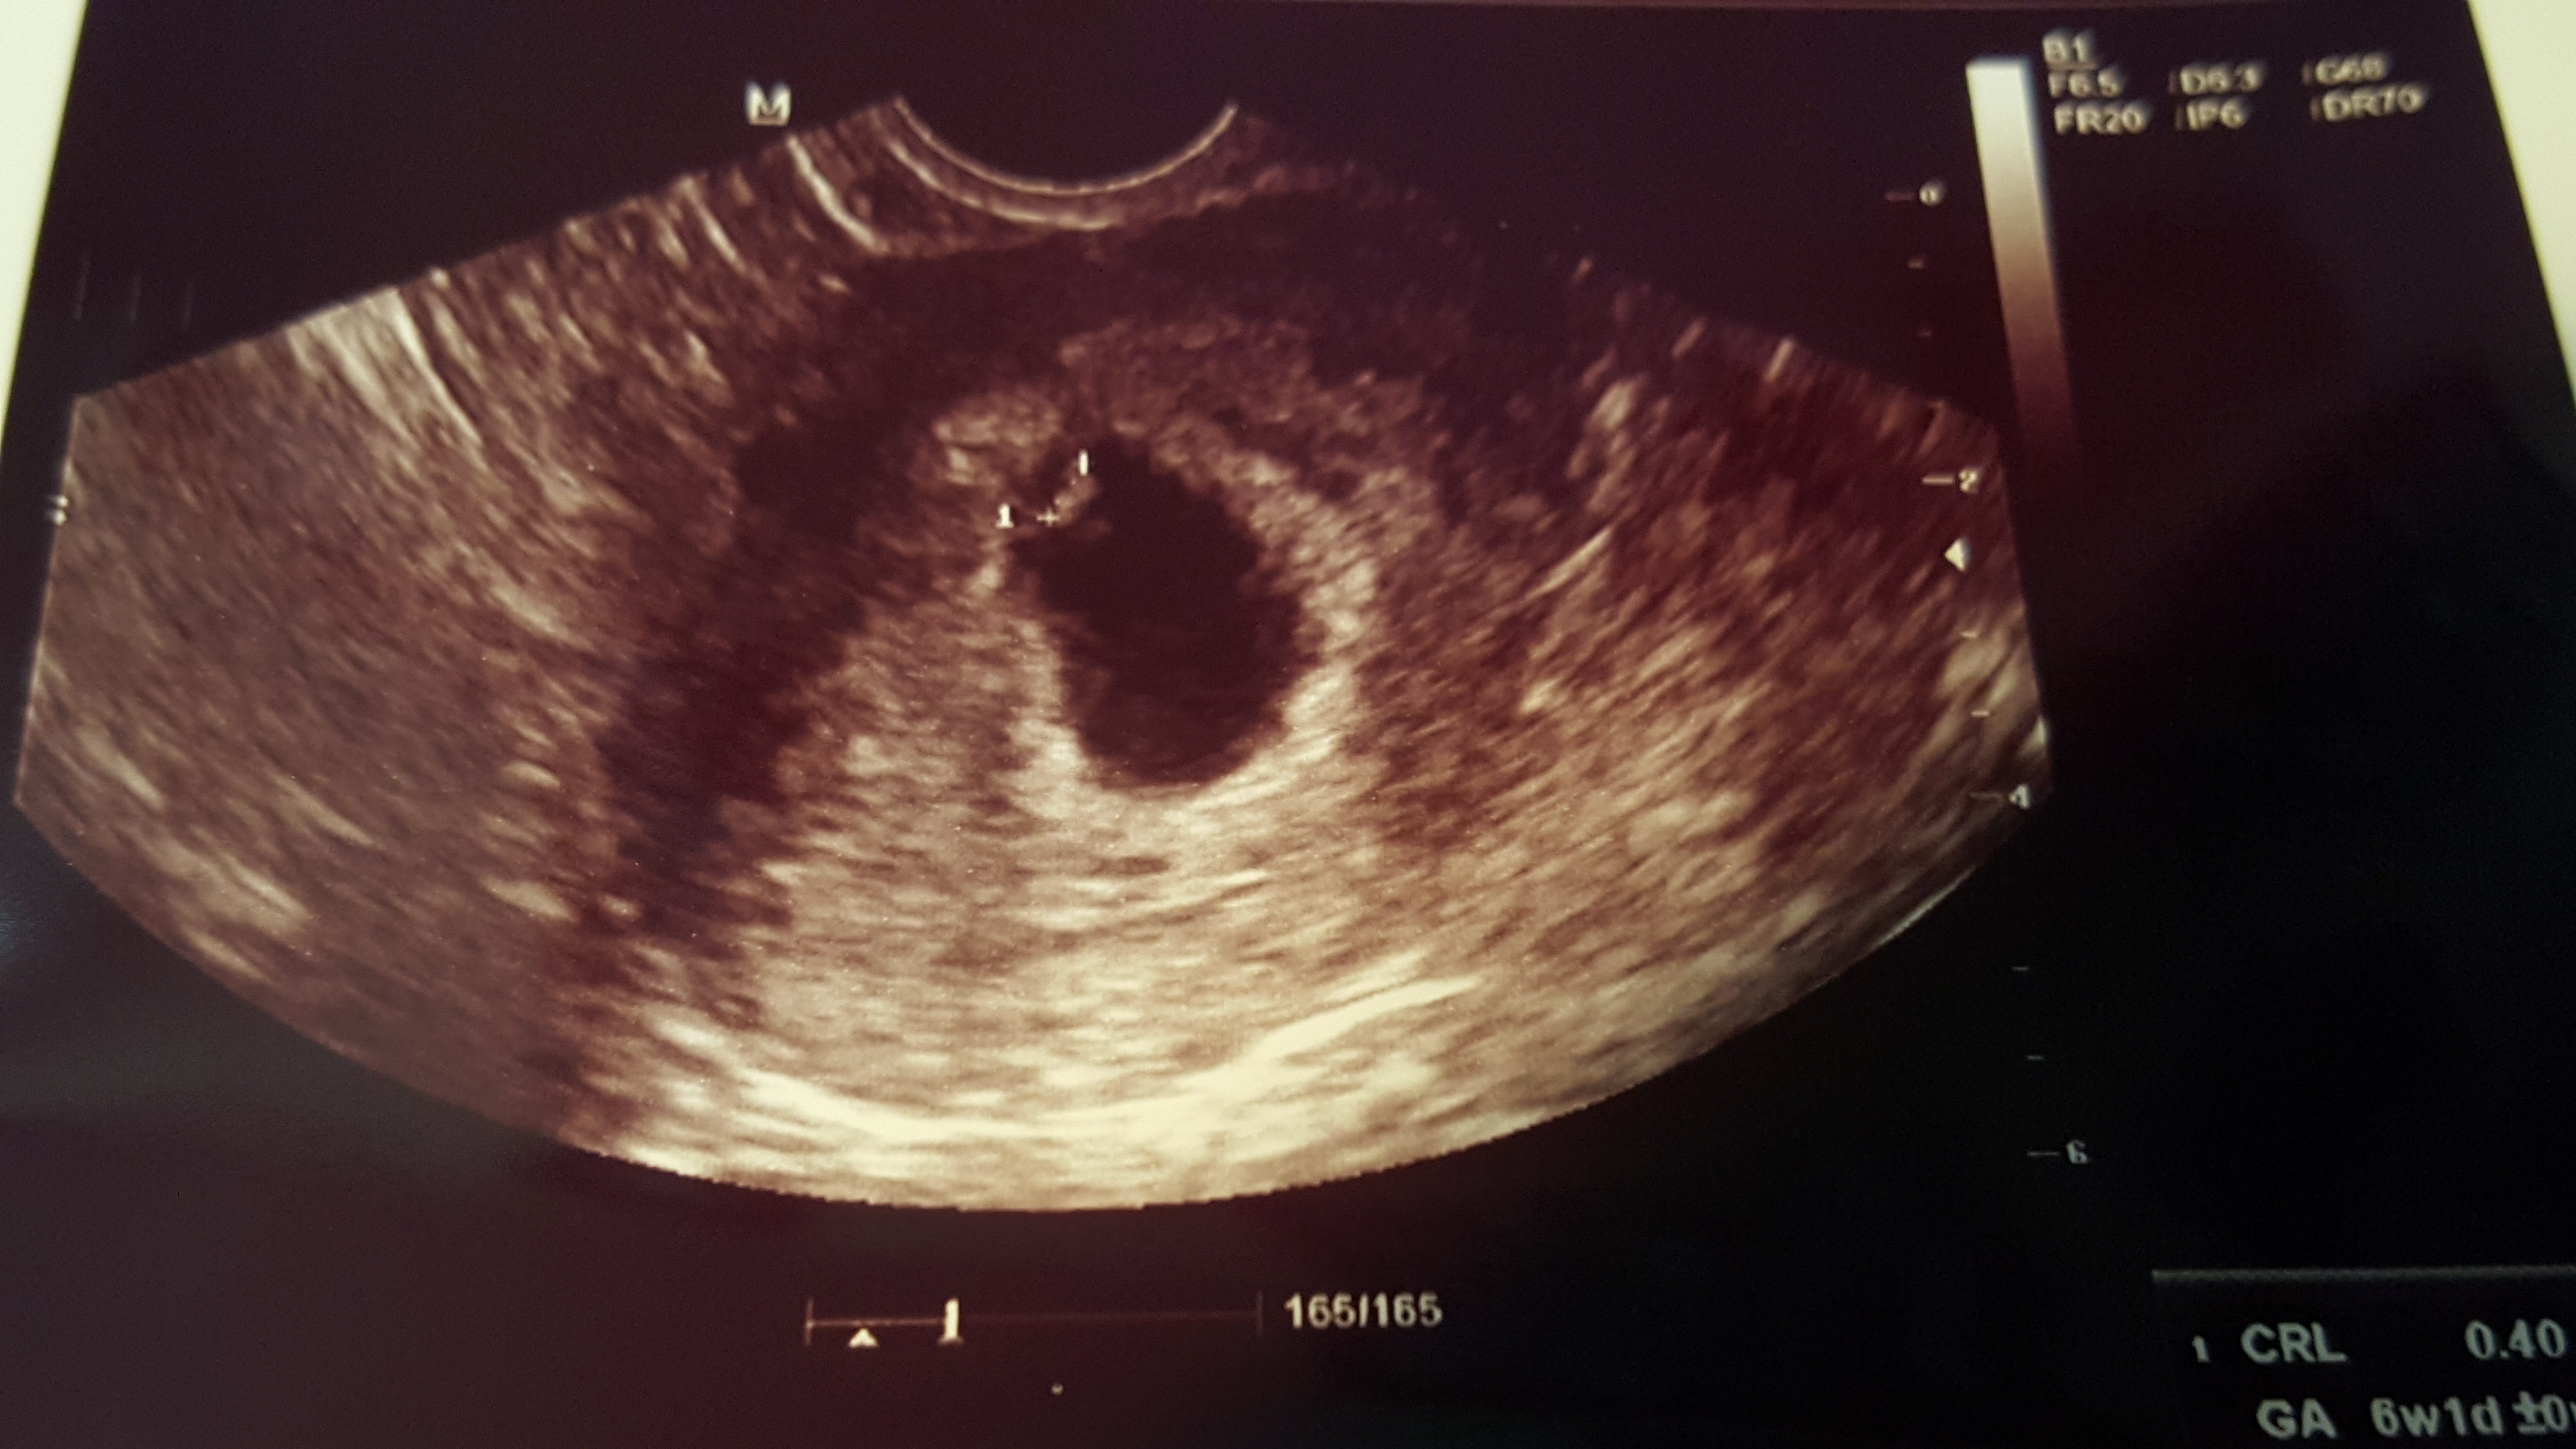

We had our first ultrasound today. Measured at 6 was 3 days which is pretty much right on track. He/she is tiny but we already heard the heartbeat at 124 bpm. We have one every week from now until the end of the first trimester so can't wait to watch the growth.